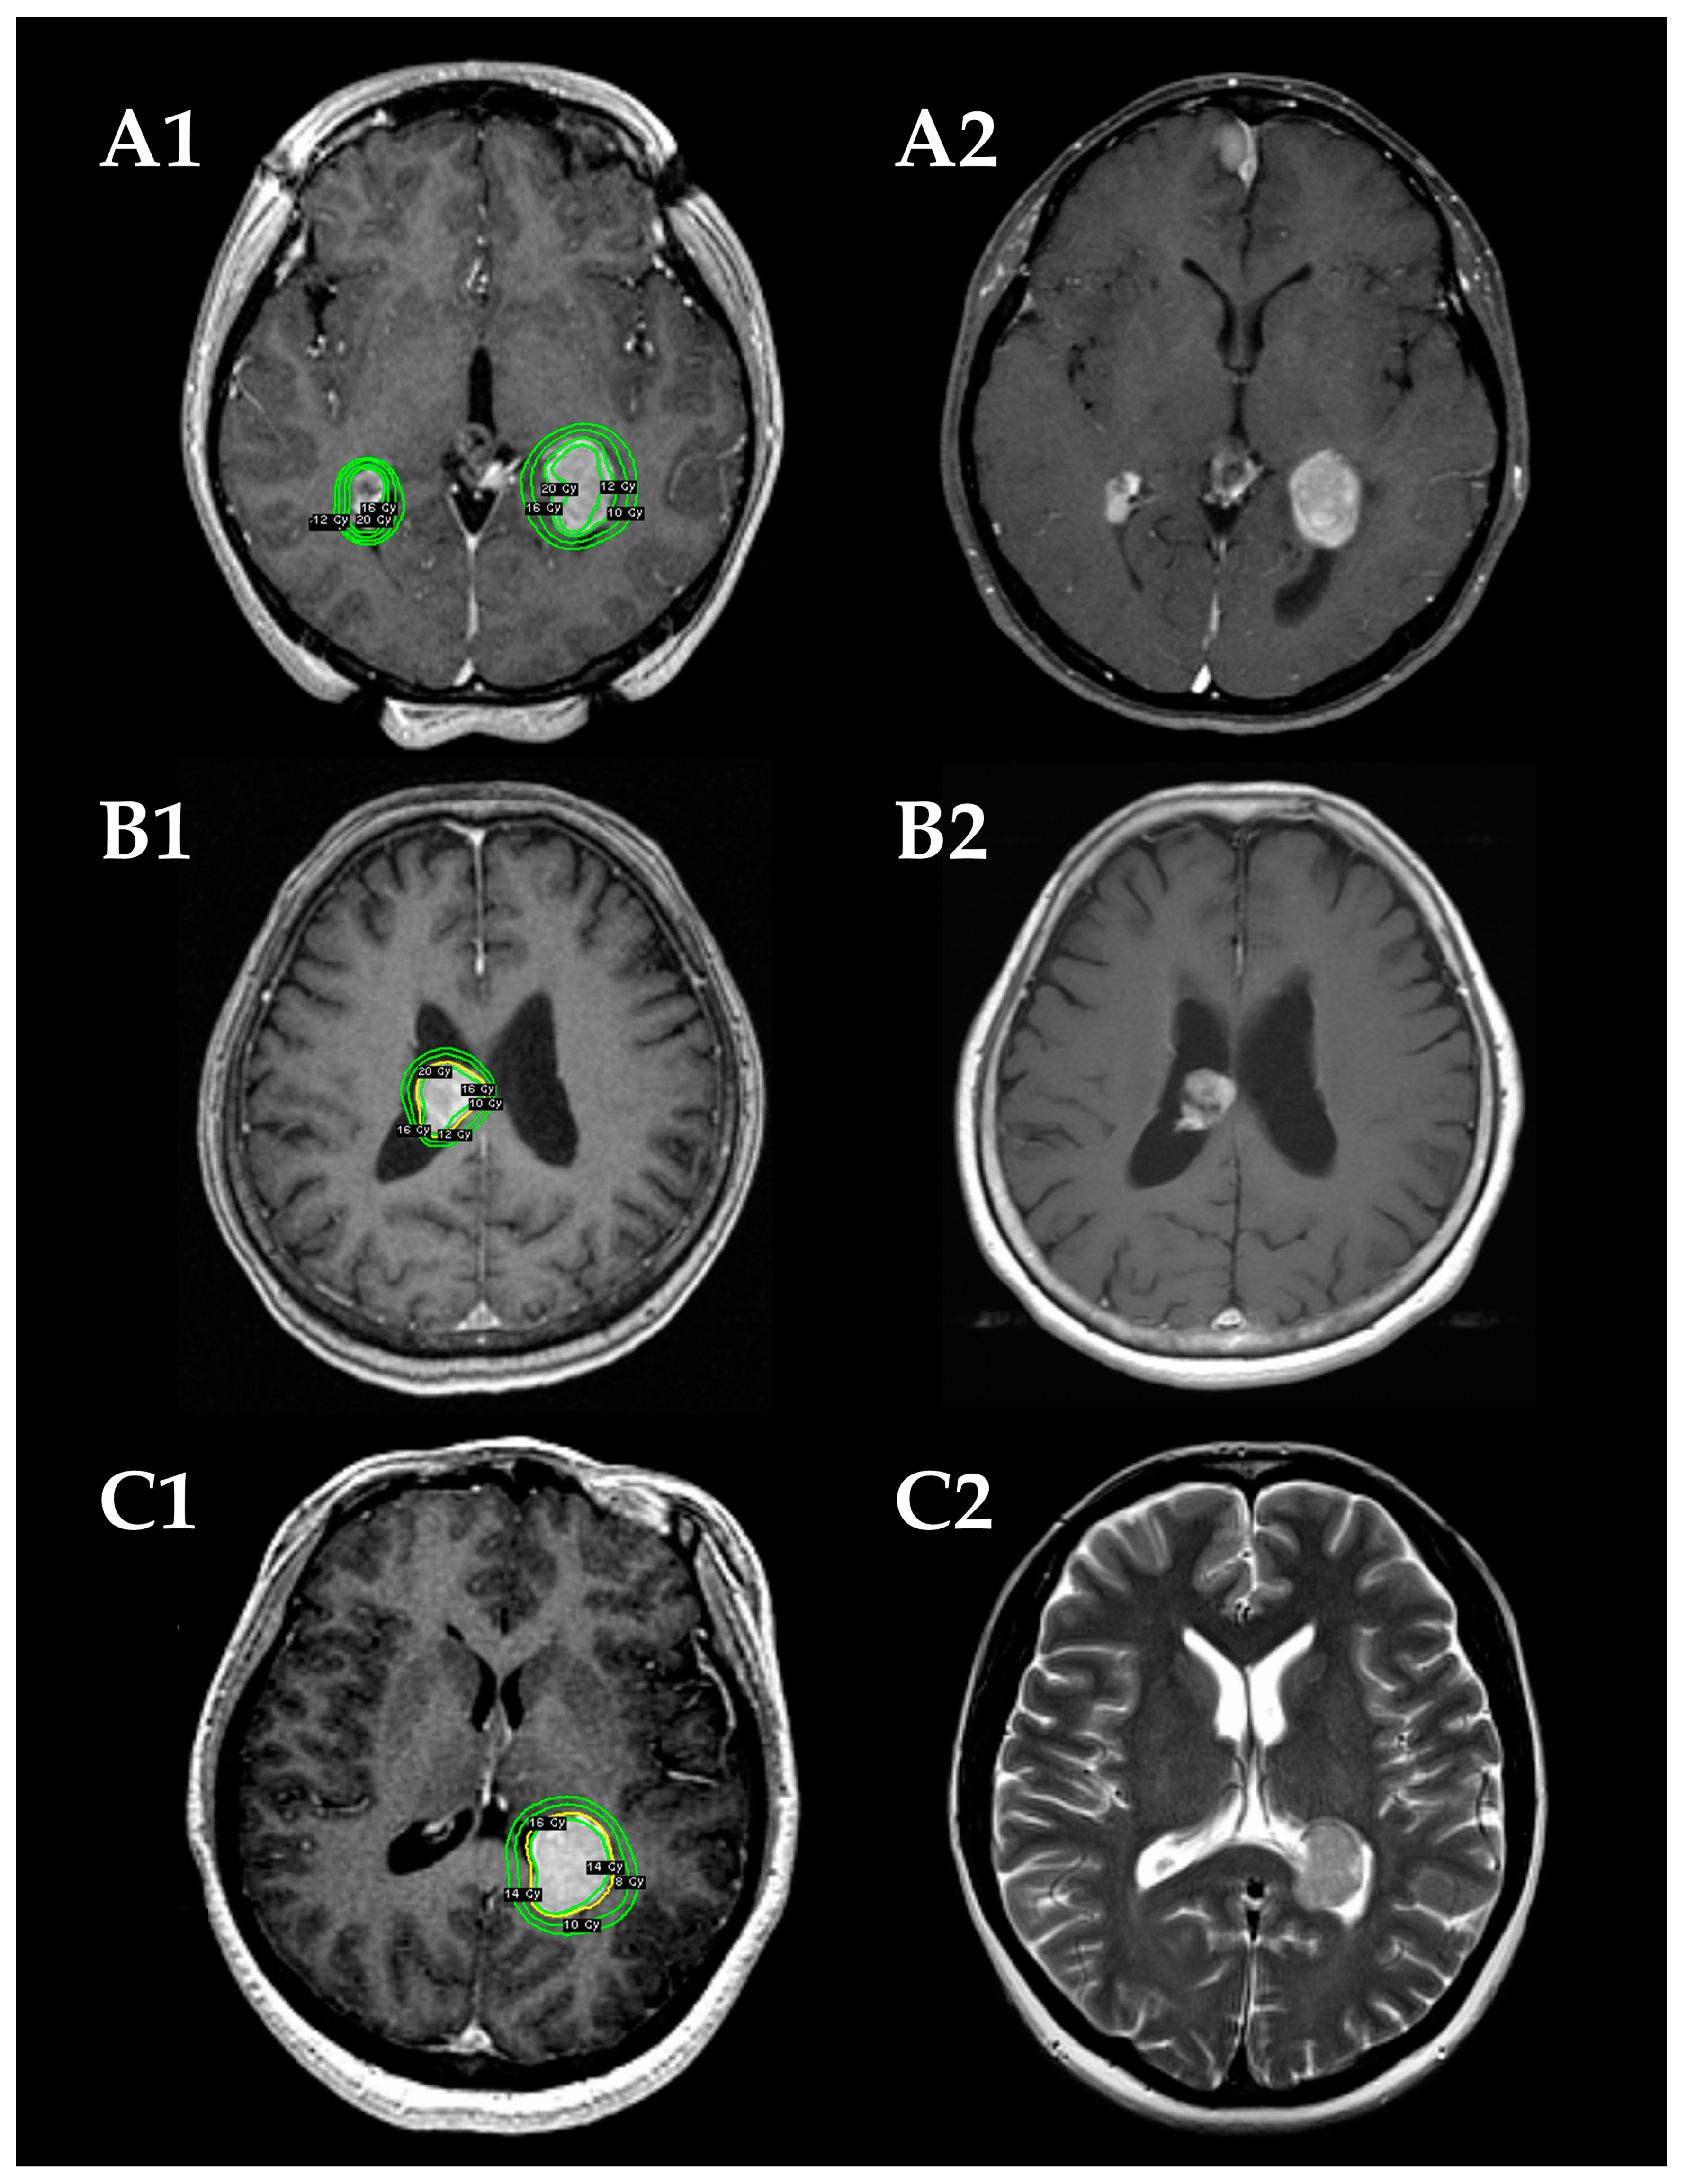

The Leksell Gamma Knife (Elekta Instruments, Stockholm, Sweden) was used for all SRS procedures. The detailed treatment process has been previously reported [15,16]. After head fixation using a Leksell frame (Elekta Instruments), stereotactic imaging (computed tomography [CT] before July 1996, magnetic resonance imaging [MRI] between August 1996 and January 2018, followed by cone-beam CT) was performed to obtain precise tumor data. Dedicated neurosurgeons and radiation oncologists performed radiosurgical planning using commercially available software (KULA planning system until 1998 and Leksell Gamma Plan thereafter [Elekta Instruments]). In principle, 16 Gy before 2010 and 14 Gy thereafter were administered to the tumor margin using a 50 ± 5% isodose line. Representative cases are shown in Figure 1.

Figure 1.

Radiosurgical plans (A1–C1) and follow-up magnetic resonance images (MRIs) (A2–C2) in three demonstrative patients. (A) A 31-year-old woman with NF2-related bilateral intraventricular meningiomas (IVMs) in the trigones of the lateral ventricles (cases 7 and 8). The tumors are stable in size on a follow-up MRI at 21 months after the stereotactic radiosurgery (SRS). (B) An 80-year-old woman with a sporadic IVM in the body of the right lateral ventricle (case 9). Tumor shrinkage is confirmed on a follow-up MRI at 109 months after the SRS. (C) A 50-year-old woman with a sporadic IVM in left trigone (case 11). Tumor shrinkage is confirmed on a follow-up MRI at 35 months after the SRS.